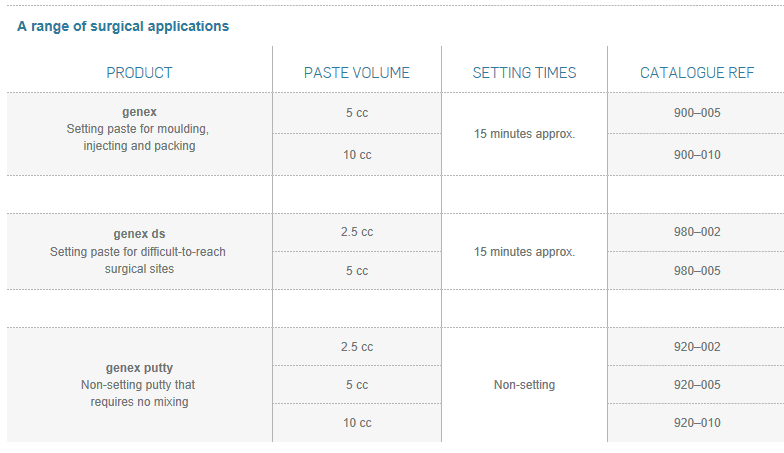

genex is versatile and easy to prepare. It comes as a paste or putty in a range of volumes. The paste sets within 15 minutes, at body temperature, and can be digitally implanted or injected in difficult-to-reach sites, or minimally invasive procedures.

genex

genex ds